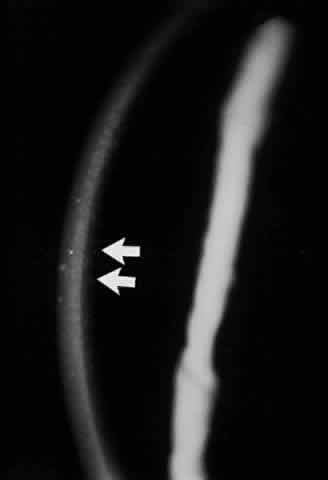

Clinically, the ocular disease in cicatricial pemphigoid (OCP) may present unilaterally in the form of a chronic, recurrent catarrhal conjunctivitis, but it eventually becomes bilateral. Subepithelial fibrosis is characteristic of stage 1 of OCP (Fig. 7). Stage 2 shows fornix foreshortening (Fig. 8), and symblepharon formation is the hallmark of stage 3 (Fig. 9). Stage 4, end-stage disease, is characterized by ankyloblepharon and surface keratinization (Fig. 10). Obstruction of the lacrimal ductules and meibomian gland ducts eventually produces an unstable tear film and progressive sicca syndrome, but it is to be emphasized that OCP is not a dry-eye syndrome until late in the disease course.20 Trichiasis and entropion occur because of the subepithelial fibrosis, with eventual keratopathy, corneal neovascularization, and corneal ulceration and scarring.20

Fig. 7. Stage 1 cicatricial pemphigoid, with cicatrizing conjunctivitis, and fine striae-type areas of subepithelial fibrosis, but without evidence of shrinkage of the conjunctiva.